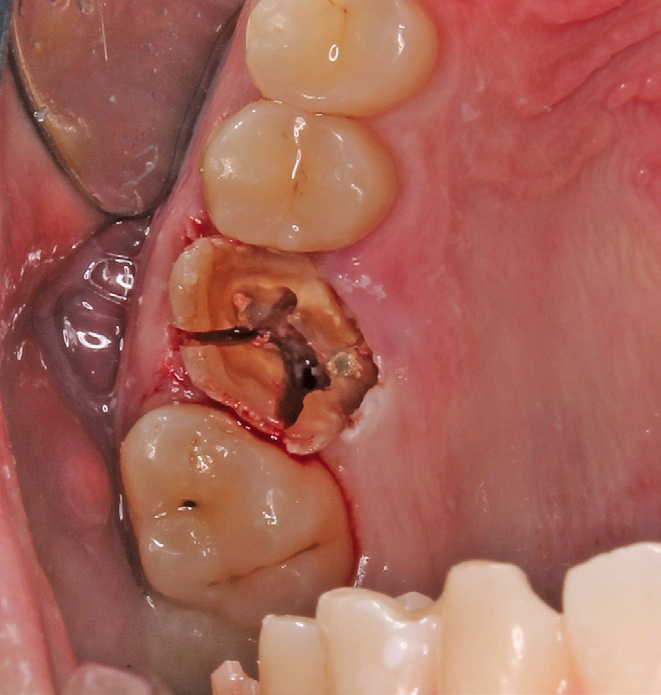

Die Operation erfolgte in Lokalanästhesie (Ultracain® D/S forte, Aventis, Frankfurt) in Form einer Infiltrationsanästhesie bukkal und palatinal der Region 26. Mittels der Instrumentenspitze EXP4-L (Piezosurgery, Mectron, I-Genua) wurden die dentogingivalen Fasern vorsichtig durchtrennt und der Desmodontalspalt geweitet (Abb. 5 und 6). Nach Durchtrennung der Wurzeln wurde der Zahn mit einer Extraktionszange aus dem gelockerten Zahnfach vollständig entfernt (Abb. 7 und 8).

Nach der Präparation des Weichgewebes wurde ein Mukoperiostlappen mit Hilfe der Instrumentenspitze PR2 (Piezosurgery, Mectron, I-Genua) vorsichtig präpariert, um eine suffiziente Deckung der Wunde zu gewährleisten (Abb. 9 und 10). Nach Vorbereitung des Weichgewebes wurde die 3D-gedruckte Bohrschablone auf den Zahnbogen gesetzt und ein Führungsschlüssel mit 2 mm Durchmesser eingesetzt, durch den ein Osteotom einführt wurde, um eine Führung für den nachfolgenden Trepanbohrer in den Knochen kondensierend zu präparieren (Abb. 11). Entlang des Führungskanals wurde das Bett für den allogenen Knochenring (maxgraft bonering; botiss biomaterials GmbH, Berlin) trepaniert (Abb. 12). Der allogene Knochenring wurde extraoral passgenau zugeschnitten und anschließend in die Extrationsalveole platziert (Abb. 13 und 14). Mittels eines breiten Osteotoms wurde der Knochenring samt basalem Knochensegment schablonengestützt nach apikal in den Sinus maxillaris verschoben. Ein parallelwandiges Implantat (Bone Level Roxolid, SLActive, Straumann) mit einem Durchmesser von 4,1 mm und einer Länge von 10 mm wurde zentral in den positionsstabilen Knochenring primärstabil inseriert, mit einer Fixierungkappe (Durchmesser 5,5 mm) versehen und die umliegende Extrationsalveole mit granulärem bovinem Knochenersatzmaterial ausgefüllt (Abb. 15-17). Anschließend wurde die Wunde mit dem Mukoperiostallappen gedeckt und speicheldicht vernäht (Abb. 18). Zur postoperativen Kontrolle wurde ein Orthopantomogramm aufgenommen, auf dem keinerlei Verletzungen benachbarter anatomischer Strukturen zu erkennen sind (Abb. 19). Es folgten zwei radiologische Verlaufskontrollen, vier und sechs Monate nach dem Eingriff, ohne Besonderheiten (Abb. 20 und 21).